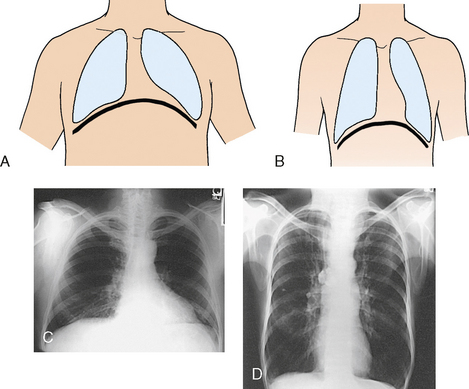

The position of the diaphragm varies with body habitus: It is at a higher level in hypersthenic patients and at a lower level in asthenic patients (Fig. 9-9). In sthenic patients of average size and shape, the right side of the diaphragm arches posteriorly from the level of about the 6th or 7th costal cartilage to the level of the 9th or 10th thoracic vertebra when the body is in the upright position. The left side of the diaphragm lies at a slightly lower level. Because of the oblique location of the ribs and the diaphragm, several pairs of ribs appear on radiographs to lie partly above and partly below the diaphragm.

Fig. 9-9 Diaphragm position and body habitus. A, A hypersthenic patient has a diaphragm positioned higher. B, An asthenic patient has a diaphragm positioned lower. C, Chest radiograph of a hypersthenic patient. D, Chest radiograph of an asthenic patient. Note position of diaphragm on these extremely different body types.

The position of the diaphragm changes considerably with the body position, reaching its lowest level when the body is upright and its highest level when the body is supine. For this reason, it is desirable to place the patient in the upright position for examination of the ribs above the diaphragm and in a recumbent position for examination of the ribs below the diaphragm.

The respiratory movement of the diaphragm averages about 1½ inches (3.8 cm) between deep inspiration and deep expiration. The movement is less in hypersthenic patients and more in hyposthenic patients. Deeper inspiration or expiration and greater depression or elevation of the diaphragm are achieved on the second respiratory movement than on the first. This greater movement should be taken into consideration when the ribs that lie at the diaphragmatic level are examined.